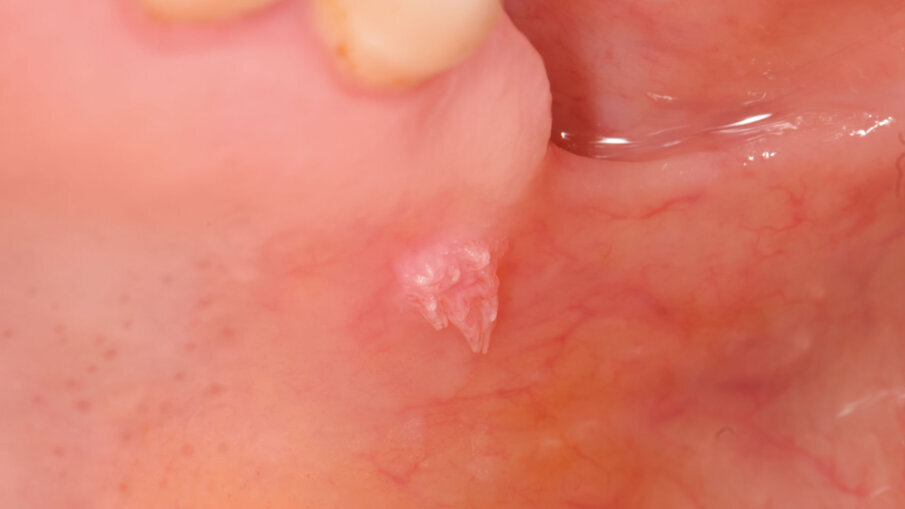

Una paziente di 42 anni si è presentata per una visita odontoiatrica specialistica. Dopo aver raccolto un’anamnesi completa, che includeva informazioni fisiologiche e patologiche, sia remote che recenti, abbiamo proceduto con l’esame clinico, che nella nostra pratica prevede sempre una valutazione generale delle mucose, delle stazioni linfonodali e della funzionalità della deglutizione. La paziente era in ottima salute generale e orale, con un completo assetto dentario e una buona igiene orale. Durante l’ispezione, abbiamo individuato una lesione papillomatosa nella zona di transizione tra il palato duro e il palato molle sul lato sinistro (Fig. 1). La lesione, caratterizzata da villosità cheratinizzate, non presentava sanguinamento né spontaneo né contatto e non causava dolore. Alla palpazione, non abbiamo riscontrato linfonodi sublinguali, sottonucali o laterocervicali bilaterali. Abbiamo ipotizzato si trattasse di una lesione papillomatosa, ipotesi confermata successivamente dall’esame istologico.

Fig. 1 - Lesione papillomatosa tra palato duro e molle in prossimità della tuberosità.